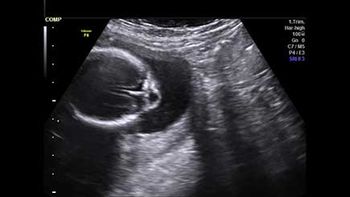

Challenge your diagnostic skills: See anything atypical with this 8-week pregnancy?